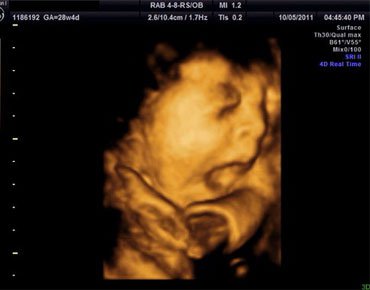

四维彩超的全称为四维彩色超声诊断仪,是目前世界上最先进的彩色超声设备,它可以做到表面显像,一些先天畸形疾病像是唇腭裂,脑膜膨出,脊柱裂等都可以清晰地反映出来,以便及时做治疗,提高优生率。

四维彩超属于表面成像,它的清晰度和准确度很高,可以为早期诊断先天性体表畸形和其他先天性疾病提供准确的科学依据,也可以分辨胎儿的性别,但是由于国家规定,若是用于非医学性操作的分辨胎儿性别是属于违法行为,因而医院做给孕妇做四维彩超时会主动避开胎儿的性别分辨。

四维彩超的用途有多种,其中最广泛的应用是孕妇的胎儿排畸排挤检查,四维彩超清晰度较高,显示准确,受到了很多人的欢迎。

四维彩超是目前世界上最先进的彩色超声设备,其特点是即时立体成像、清晰准确。四维b超不仅可以把宝宝的即时动态传递给准妈妈、还可以观察到宝宝的活动图像和在妈妈肚子里的各种神态,而且胎儿的四肢及内脏也能直接观测到,出胎儿各器官的发育情况也可以立体显示出来,这样,一些先天性畸形可见被尽早的发现,比如:对胎儿唇裂、腭裂、骨骼发育异常、心血管畸形等,从而做出更准确的早期诊断。让胎儿可以健康的生长发育。